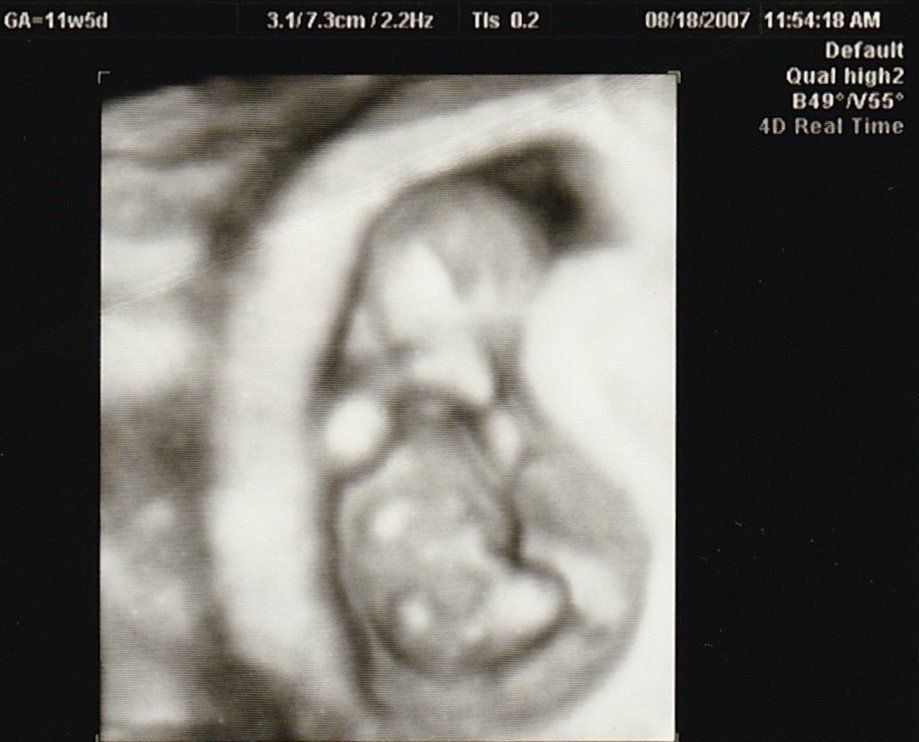

4D画像で頭、手、足を見ることができました。枝豆のような頭の形でなんだかかわいい、と早くも親バカ。この時期は、子宮がんや感染症の免疫の有無など、様々な検査を行いました。実母に、私がはしかやおたふく風邪にかかったかなどや、母がどのような妊娠・出産をしたかを教えてもらいました。